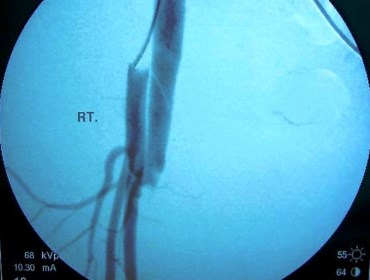

Angiography shows Femoral AV Fistula

Femoral AV Fistula Repair

2. Gunshot induced Iliac Arterio-Venous Fistula